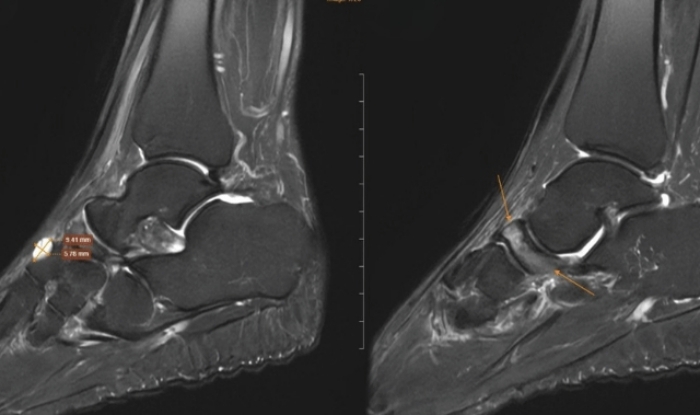

Tại cơ sở y tế, bác sĩ chỉ định chụp cộng hưởng từ để đánh giá tổn thương sâu. Kết quả, xương ghe bàn chân phải bị xẹp và biến dạng điển hình, kèm đặc xương dưới sụn và phù tủy rõ rệt. Ngoài ra, hình ảnh còn ghi nhận tổn thương thoái hóa khớp cổ chân trái, phù tủy xương sên, viêm dây chằng và dịch khớp cổ chân.

Từ sự phối hợp giữa lâm sàng và chẩn đoán hình ảnh, bệnh nhân được chẩn đoán theo dõi hội chứng Muller-Weiss bên phải, kèm phù tủy xương sên trái. Bác sĩ chỉ định điều trị nội khoa, tiêm huyết tương giàu tiểu cầu hai chân dưới hướng dẫn siêu âm, đồng thời sử dụng đế giày chỉnh hình. Sau điều trị, tình trạng đau giảm rõ rệt và khả năng vận động cải thiện.

Hình ảnh chụp MRI cho thấy những dấu hiệu đặc trưng của Hội chứng Mueller-Weiss ở chân phải.

Bác sĩ chẩn đoán hình ảnh cho biết việc phát hiện bệnh phụ thuộc nhiều vào các phương tiện cận lâm sàng. X-quang có thể cho thấy xương ghe biến dạng dạng dấu phẩy hoặc xẹp nhỏ. Chụp CT giúp đánh giá rõ tình trạng xơ cứng và phân mảnh xương. Cộng hưởng từ được xem là phương pháp nhạy nhất, phát hiện sớm phù tủy xương trước khi hình thái xương thay đổi, đồng thời đánh giá mức độ hoại tử.